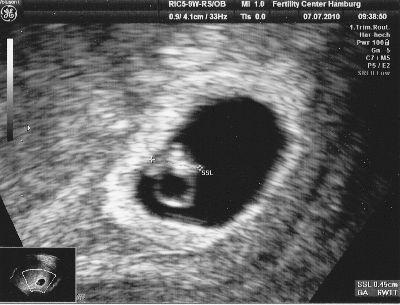

Wir gingen also nach nebenan, ich zog mich aus und setzte mich auf den Stuhl. Noch bevor er selbst etwas sagen konnte, sah ich das Kleine auf dem Bildschirm - und hielt natürlich sofort Ausschau nach dem kleinen Herzchen - und es war da! Ich konnte das Herzchen bubbern sehen...

Der Arzt bestätigte es und wir waren einfach nur glücklich!

Hier kommt noch ein kleines Foto von unserem Krümel..